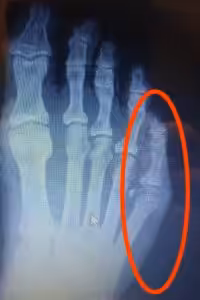

- The bone connecting to the fifth toe is called the fifth metatarsal. It is possible to develop a stress fracture or “Jones” fracture.

- A Jones fracture is a break in the base of the fifth metatarsal of the foot.

- You can feel it on the side of your foot right around the middle.

- This is a notoriously difficult part of the foot to heal because the Peroneus Brevis Muscle is always pulling it apart.